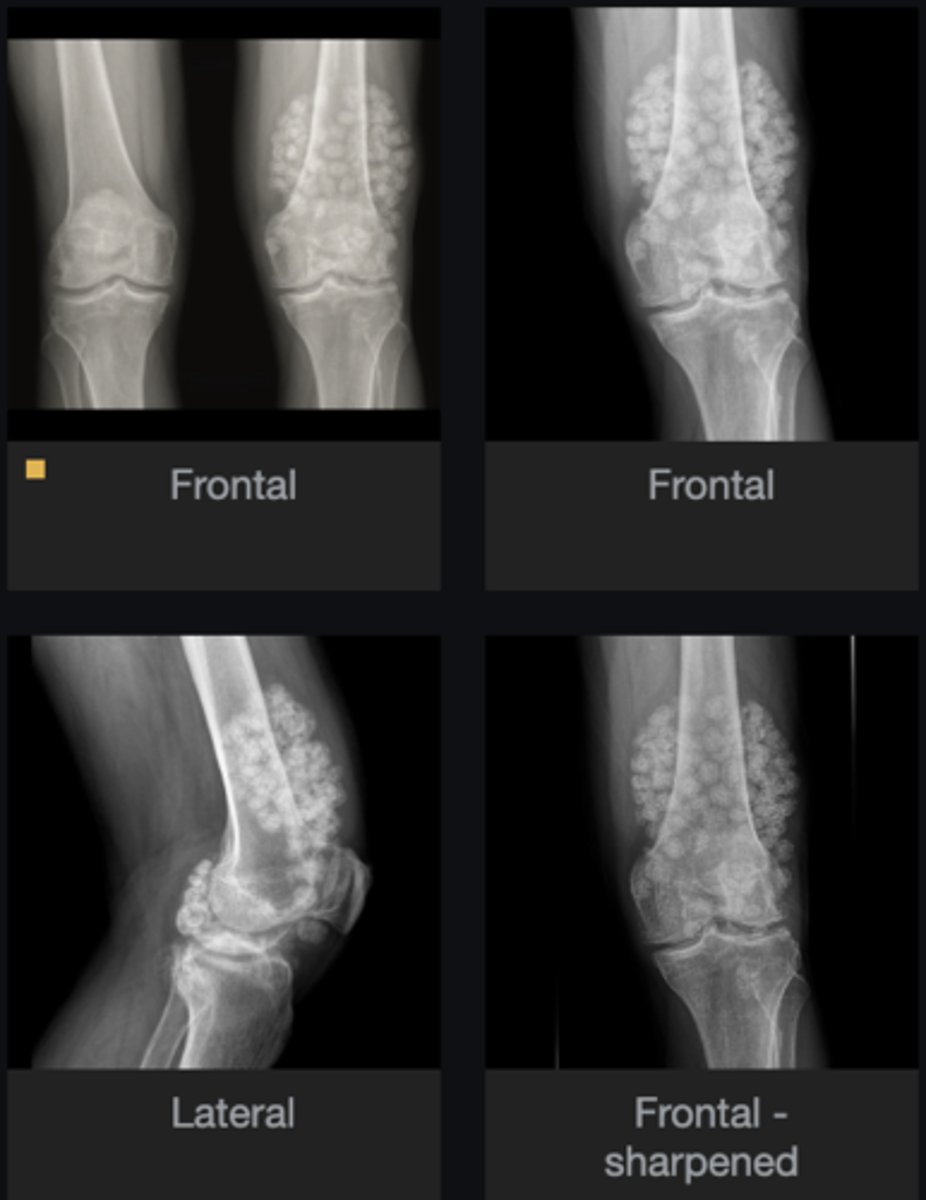

- Subluxation

- Osteophytes

- Subchondral sclerosis

- Non-uniform loss of joint space (medial tibiofemoral joint)

Describe findings

Osteoarthrosis

Diagnosis?

Patellar tooth sign

How would you describe the anterior aspect of the patella and what does it indicate?